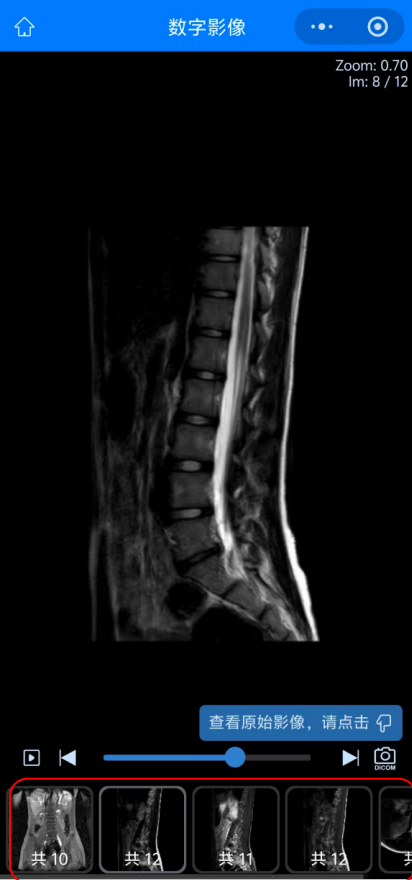

05 而點擊“查看影像”后查看到的患者的影像圖像,可以選擇下方紅色方框內(nèi)不同影像檢查或圖象處理方法來查看不同影像圖像。

09 如何進(jìn)行圖像下載:首先在查看圖像功能內(nèi)點擊右下方照相機圖標(biāo),進(jìn)入“查看原始影像”。